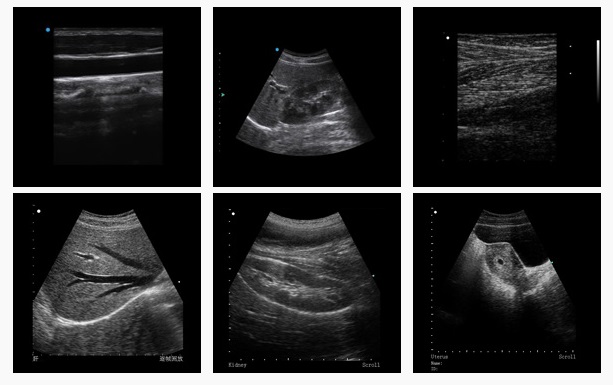

The CTS-5500V is a high-end digital veterinary ultrasound imaging system. It can be equipped with a variety of special probes, meeting the examination and diagnosis requirements for different animals. The system plays an important role in injury diagnosis of joint and tendon, organ disease diagnosis such as cardiology, pregnancy check, ovarian growth check for increasing conception rate and litter size, as well as biological engineering research such as assisting embryo transplantation.

Accurate beam forming and signal processing, digital image acquisition Powerful System Functions User-defined Function Key:The user can assign a frequently-used function (e.g. BPD) on a certain key (e.g. F1), so as to address doctors’preferential clinical demands. Perfect Document Management System Extensive Clinical Application and Abundant Software High-Density Broadband Five-frequency Probes | ||